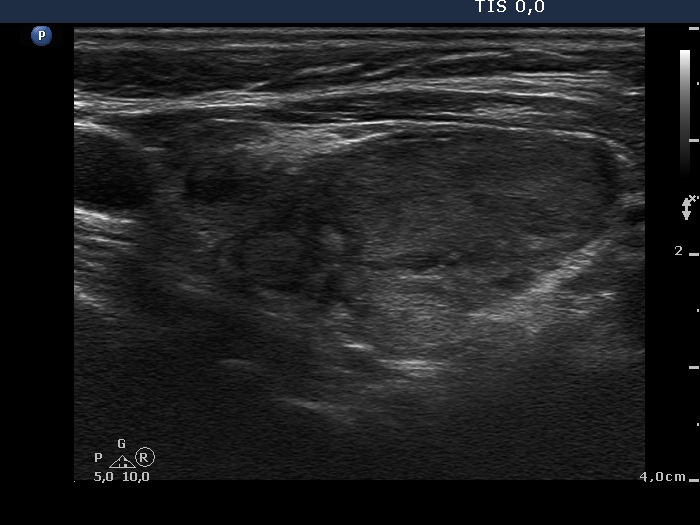

Case cons100_010 (ultrasonographic picture 6)

Left lobe, longitudinal view. While the lesion seemed to be a nodule in a pathological sense on transverse scan, we may have doubt faced with this section. The lesion has irregular shape and has a similar presentation to that of other smaller echonormal areas in the lobe.